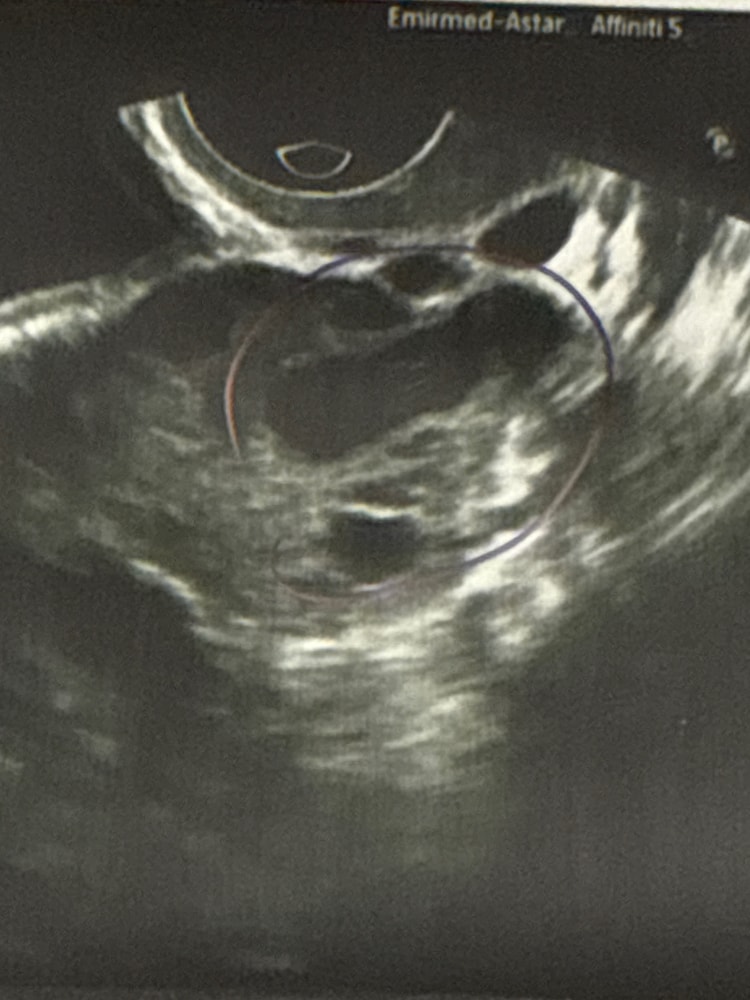

Ару, а вот второе (сегодняшнее) Изображение

Ару, тут да, ДФ. Внизу вообще не понятно, тёмное фото размытое такое(